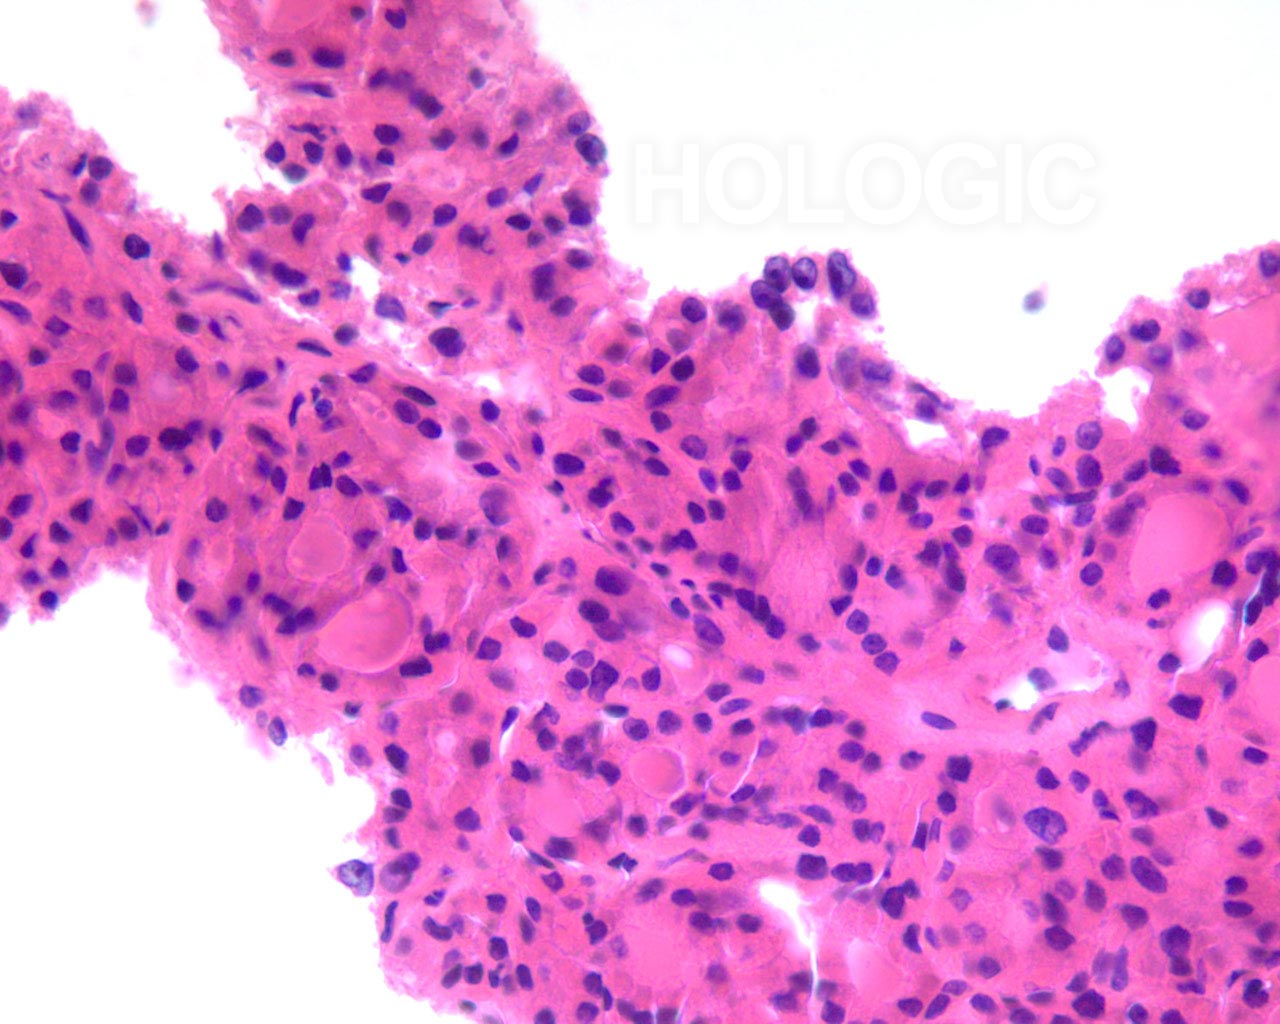

Zoals hieronder wordt beschreven, moet de morfologie van de kern worden beschreven om een papillair schildkliercarcinoom uit te sluiten. Of een laesie microfolliculair of macrofolliculair is, houdt rechtstreeks verband met de hoeveelheid colloïde en de verhouding folliculaire cellen ten opzichte van colloïd. In het algemeen zijn neoplasmen van het folliculaire type microfolliculair met weinig dicht colloïd [2]. Papillaire schildkliercarcinomen kunnen zowel micro- als macrofolliculair zijn [2]. Benigne folliculaire nodulen zijn meestal macrofolliculair en vertonen vaak cystische degeneratie [2, 3]. De cystische degeneratie in benigne folliculaire nodulen ziet eruit alsof het een veneuze stasiscomponent heeft en vertoont oedemateus waterig colloïd met hemosiderine. Papillaire schildkliercarcinomen vertonen ook vaak macrofagen met hemosiderine [2].Een dergelijke cystische degeneratie is echter naar men zegt erg ongebruikelijk bij folliculaire neoplasmen [2, 3],en dat is ook onze ervaring. Daarom vormt de aanwezigheid van hemosiderine na uitsluiting van een papillair schildkliercarcinoom (op basis van de afwezigheid van de karakteristieke kenmerken van de kern die hieronder worden beschreven), sterk bewijs voor een benigne folliculaire laesie. Lymfocyten worden vaak met plasmacellen en fragmenten van germinale centra in lymfocytische thyroïditis waargenomen, maar ze zijn zeldzaam bij folliculaire neoplasmen [2], zelfs folliculaire neoplasmen die in de context van lymfocytische thyroïditis ontstaan. Lymfocyten en plasmacellen komen echter relatief vaak voor bij papillaire schildkliercarcinomen. Benigne folliculaire laesies tonen gewoonlijk van groep tot groep enige variatie in de cytologische kenmerken en vormen dus geen monomorfe populatie.

In dit hoofdstuk worden sommige van deze voordelen geïllustreerd. In het algemeen vertonen neoplastische hürthlecelveranderingen of focaal reactieve lege plekken in de kern die duiden op een papillair schildkliercarcinoom, een spectrum aan veranderingen tonen die zich over het bereik van een enkele follikels met normaal uitziende folliculaire cellen vermengen. In celblokken is het mogelijk te zien hoe de reactieve veranderingen ruimtelijk verband houden met gebieden waarin lymfocytische vernietiging van de follikels plaatsvindt, of gebieden in een benigne colloïde nodule die leeggehaald zijn en de herstelreactie oproepen die lijkt op een papillair schildkliercarcinoom. In tegenstelling daarmee vertonen neoplastische hürthlecellen of papillaire schildkliercarcinomen vergeleken met benigne folliculaire cellen een abrupte (klonaal uitziende) overgang die geen duidelijk verband houdt met een lymfocytisch infiltraat.